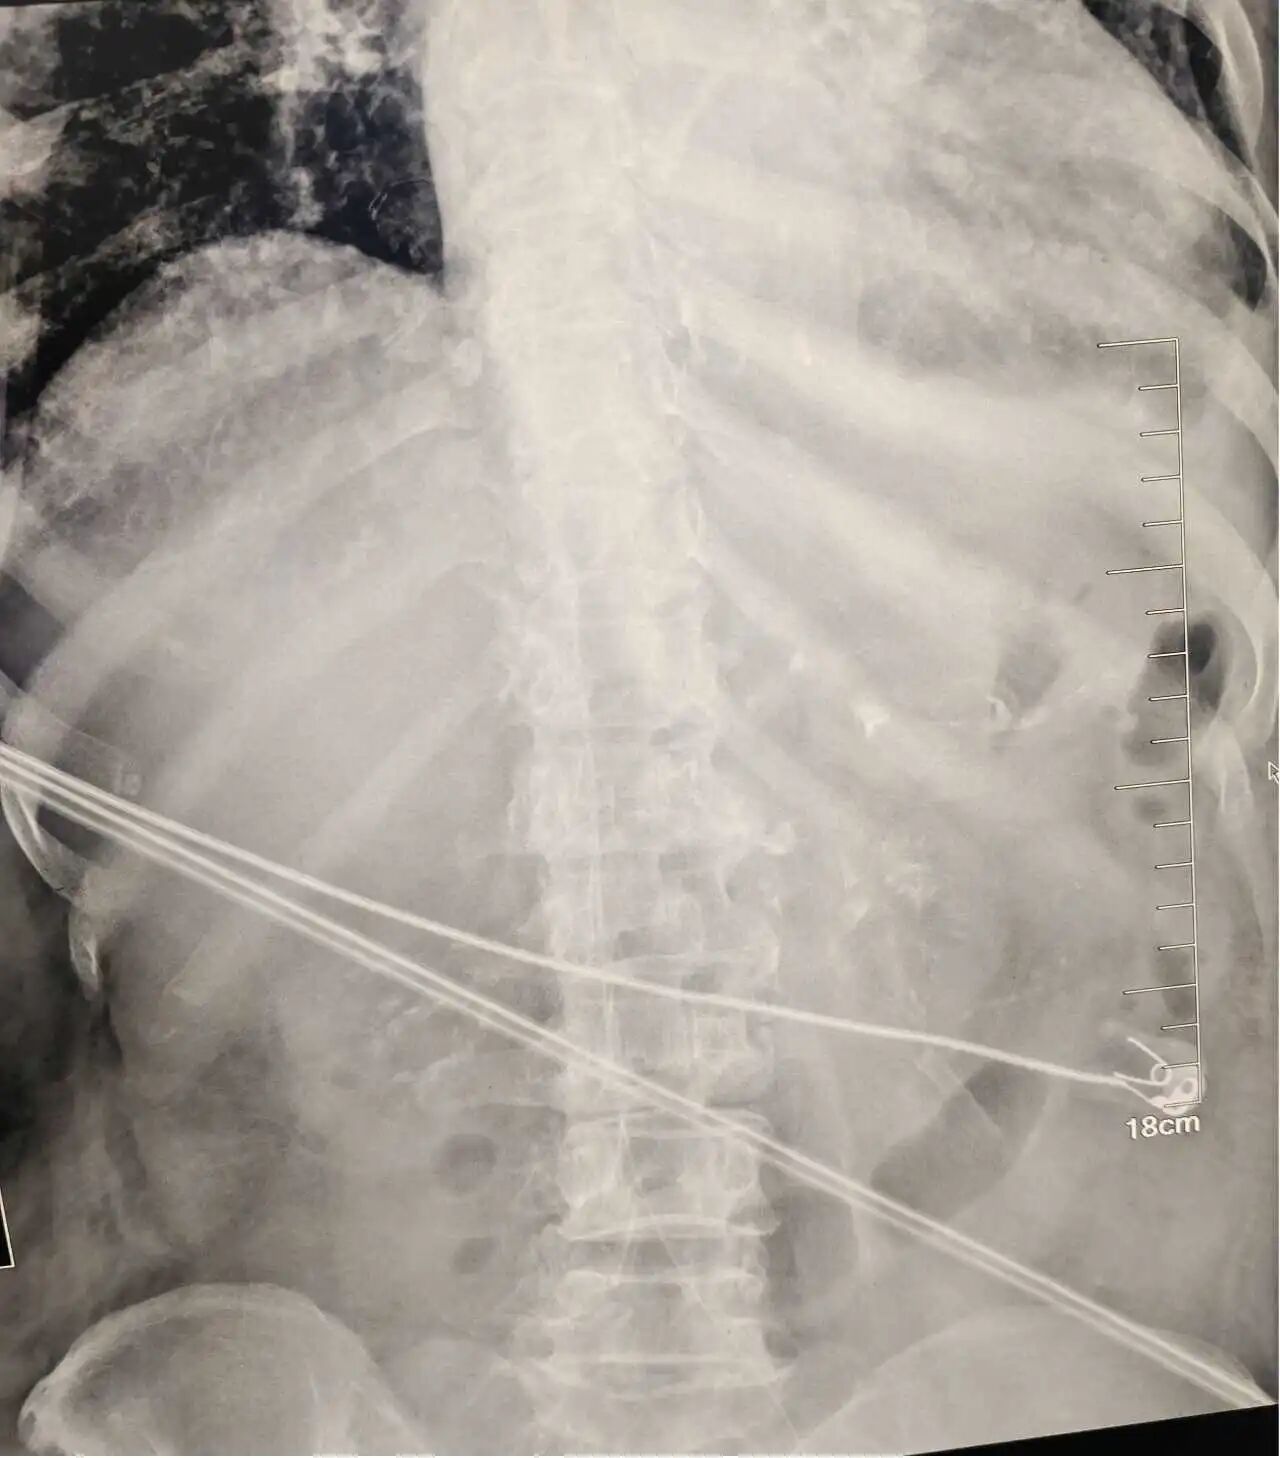

该方案精准避开了患者已有血管通路,完美契合了长期留置的治疗需求,为患者量身打造了安全可靠的生命通道。在肿瘤血液科周文雅的密切配合下,护理门诊王小霞成功实施了我院首例下肢 PICC 深静脉置管术!

此次技术的成功实施填补了我院在特殊部位 PICC 置管领域的技术空白,不仅标志着我院静脉治疗水平实现新跨越,同时也为血管条件复杂的患者开辟了全新的治疗路径。